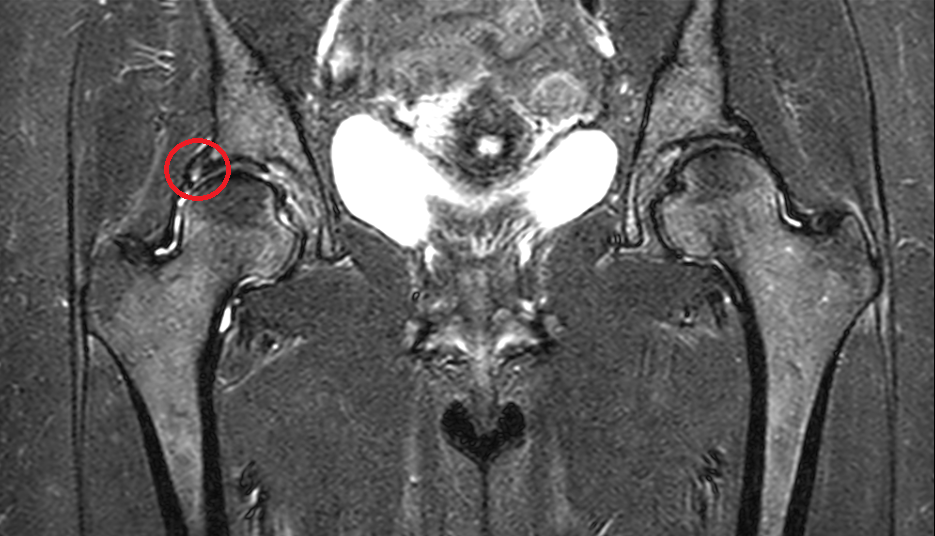

Već na drugoj terapiji imali smo nalaz MR-a koji je govorio u prilog cističnim promjenama labruma uz dojam prekida u kontinuitetu konture labruma sa zglobne (artikularne) strane u segmentu dužine 10mm.